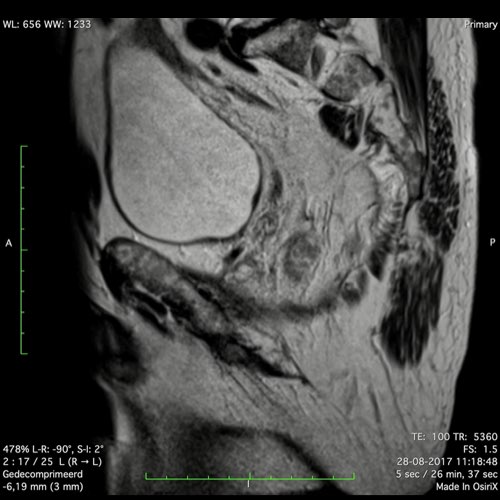

Hình ảnh

Các hình ảnh được cung cấp cho thấy ung thư biểu mô tế bào nhẫn với tình trạng dày lan tỏa thành trực tràng, hình ảnh bia bắn điển hình, và sự xâm lấn mỡ mạc treo trực tràng.